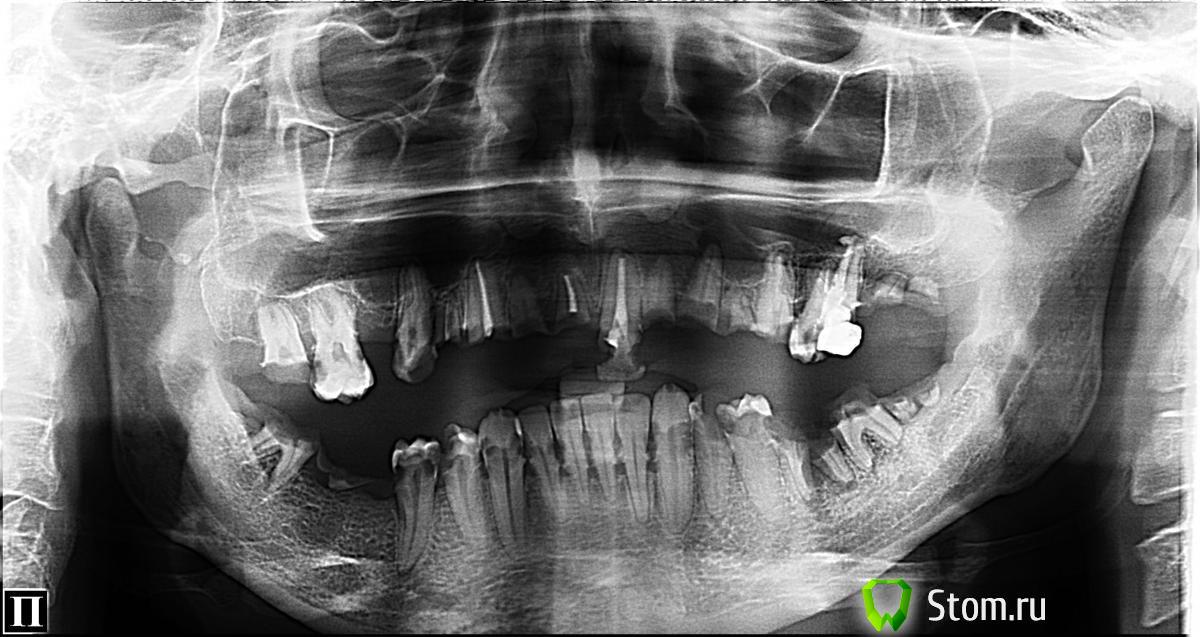

FBR Опубликовано 22 марта, 2012 Поделиться Опубликовано 22 марта, 2012 (изменено) Будет вот так. Изменено 22 марта, 2012 пользователем FBR 1 Ссылка на комментарий